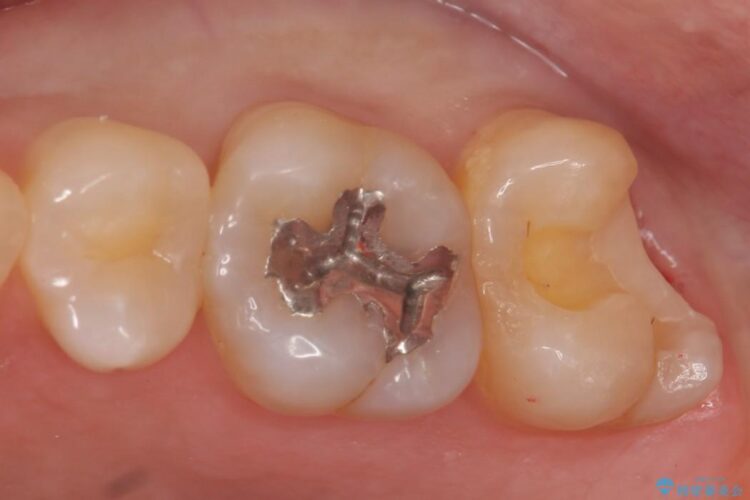

ゴールドインレー

ゴールドインレーはセラミックより強度高く、使用される金合金や白金加金は汚れの付きにくいという特徴を持っており、耐用年数が長いことが特徴としてあります。特に奥歯など強く力が欠けられる箇所に適しています。

反対にデメリットして金属であるため審美性に欠けるという点があります。